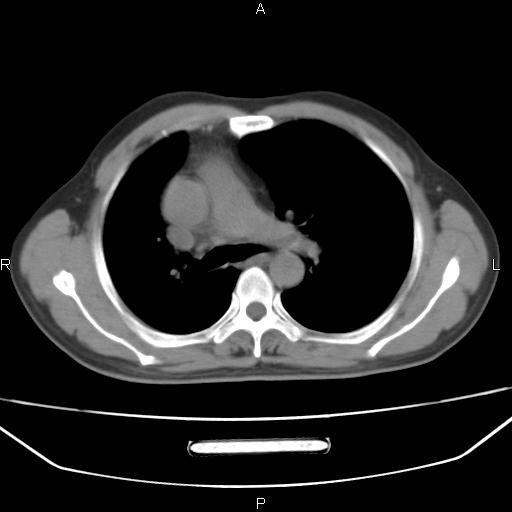

患者,男。50岁。近几日有咳嗽症状,无其他不适,既往病史无,考虑膈疝。请前辈们看看指导指导。

膈膨升,左下肺通气不良,膈肌好像还完整。

考虑左侧膈疝。

左侧膈疝。

符合隔膨升,膈肌较完整。